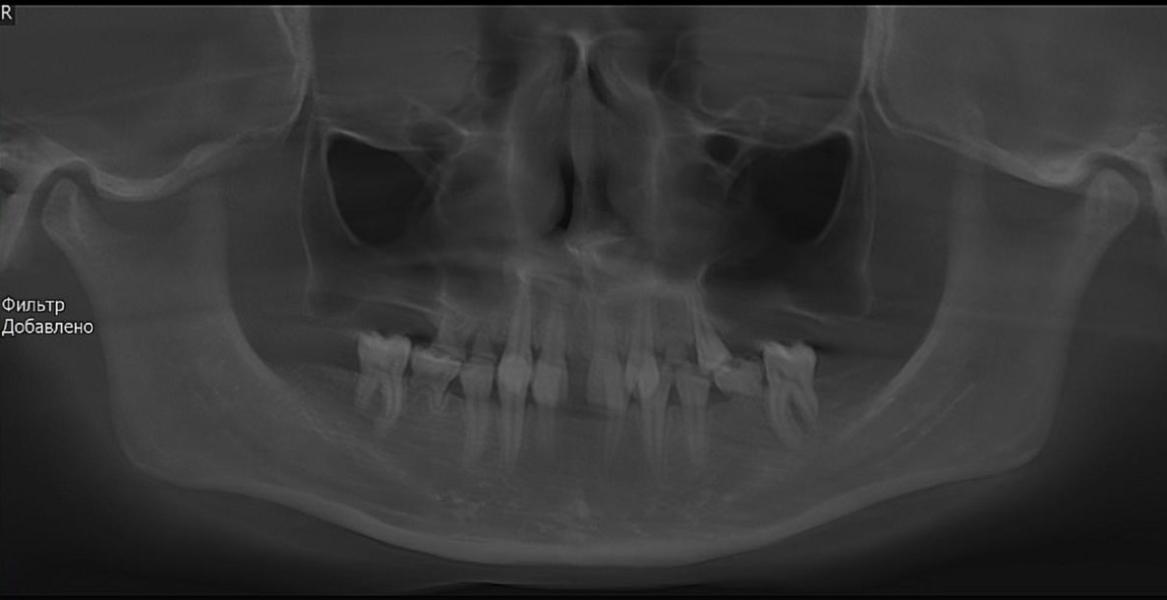

Сейчас работаю с очень редким клиническим случаем: отсутствие 11 постоянных зубов, генетически обусловленным (то есть у кого-то у родителей есть эта проблема с рождения).

Это значит, что у пациента НЕТ и НЕ будет половины зубов. На фото видны зубы, но большинство из них МОЛОЧНЫЕ, которые скоро выпадут. От того , что нет зачатков постоянных зубов происходит деформация челюстей; страдает эстетическая функция и, безусловно, пациент не может эффективно пережевывать пищу.

Пациенту 16 лет. Я рада, что пациент попал ко мне сейчас, не позднее. Все ортодонты ДО МЕНЯ отправляли еще подрасти и дождаться 18 лет, когда можно проводить имплантацию. НО❗️ я приверженец мягкого поэтапного профилактического лечения: когда мы не ждём, пока сформируется еще бОльшая патология, а потихоньку решаем маленькие проблемы. Так как чем раньше начнешь, тем легче будет создать правильную функцию и эстетику.

Мы с нашими опытными врачами собрали консилиум. Подтвердили мое предположение, что ИМЕННО сейчас ортодонт должен начать лечение, чтобы к 18 годам мы имели хорошую кость челюстей и условия для имплантации и протезирования. Работа непростая и невероятно интересная, потому что мы делаем функцию и красоту человеку, который в самом начале своего жизненного пути. Я счастлива быть причастной к этому. Пациенту понравился мой щадящий, логичный зубосохраняющий план лечения и мы начали этот путь длиною в 4 года.